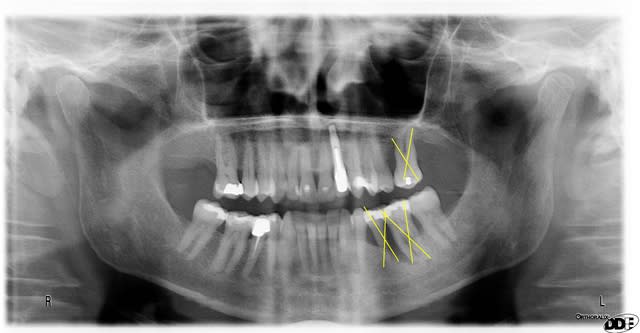

oui, Noah,voici les radiographies de ce patient

flicfac, en ce qui concerne la 46, tu as d'après ton bilan de sondage une atteinte de furcation de grade III, ce qui signifie que ton potentiel de régénération est nul.